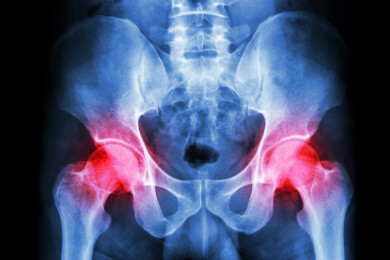

Das Hüftgelenk bildet das Zentrum der Hüfte. Becken und Oberschenkelknochen bilden dabei ein Gelenk. Durch die tägliche Beanspruchung muss das Hüftgelenk einem hohen Verschleiß standhalten, weshalb im hohen Alter oft ein künstliches Hüftgelenk eingesetzt werden muss.